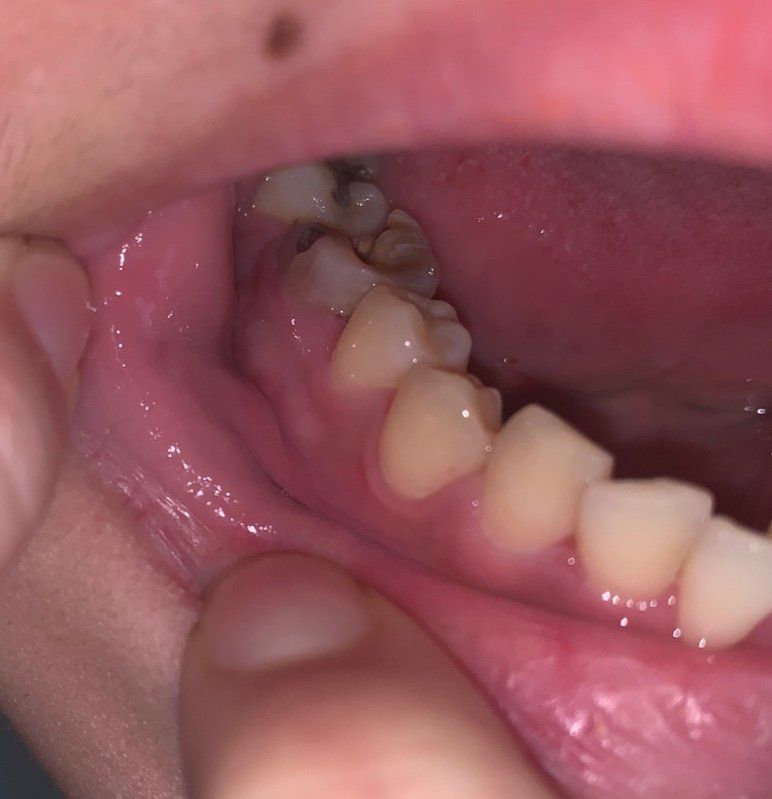

어제 10일 아침에 일어나니 볼안쪽이 심하게 부어있고 거울을 봐도 볼걸이 마냥 오른쪽 볼이 살짝 부어있는게 티가 날 정도였어요.. 그리고 침삼킬때 진저리 칠정도로 목이 아파요.. 목도 전체적으로 아픈게 아니라 오른쪽 부근만 아파요.. 따갑다는 표현이 맞을지.. 상처난데에 물 닿으면 아픈 느낌 불타는 느낌?? 무튼 침을 삼킬때 목이 너무 아파서 그냥 모았다가 한번에 삼키거나 뱉어버려요.. 어제 일요일이라 병원도 다 닫아서 탁센 먹었는데(아침에 한알 저녁에 한알 먹고 잠) 저녁쯤 되니 붓기는 좀 가라앉았어요... 근데 탁센 먹어도 침삼킬 때 목톡증은 통증 정도만 좀 낮아졌지 여전히 아팠어요..ㅠ 지금도 입술 막 움직여보면 왼쪽은 멀쩡한테 오른쪽이 많이 부어서 어금니들에 부벼대는 느낌.. 그래서 이게 이비인후과로 가야하는지 치과로 가야하는지 모르겠네요.. 사진상 보이는 어금니 깨져있는 듯한 치아는 사실 신경치료 다 끝나고 크라운으로 씌웠어야 했는데 돈이 부족하고 비싸서.. 장기간 신경치료만 마친 채 방치된 상태에요.. 그래도 신경치료를 해놔서 그런지 별다른 통증 없이 지내왔는데 갑자기 저 치아 잇몸이 하얗게 부어있고 볼안쪽도 심하게 붓고 ... 혹여나 사랑니때문인가 싶기도 하고.. 근데 왜 목은 타들어갈듯 아픈건지.. 자세한 답변 좀 부탁드려요..ㅠ 제가 월급이 한 3일 이내로 나올 듯 한데.. 여유 돈이 없어.. 몇 일이라도 이 통증을 없앨 수 있는 방법이 있다면 이것도 좀 알려주세요.. 탁센은 목통증에 잘 안드는 듯 해서요..ㅠ

사랑니로 인한 지치주위염 혹은 신경치료 중단 후 방치된 치아의 염증 재발 소견으로 보입니다.

사진으로만 봤을 경우에도 우측 하악 1대구치의 치질의 손상이 많이 되어 있는 것으로 보입니다.

신경치료를 마무리 했어도 크라운등의 보철치료를 하지 않으면 메꾼재료가 떨어지거나 안쪽으로 감염이 진행되어 치근단 염증을유발할수 있어요.

심하게 부종이 있는것으로 보입니다.

우선 정확한것은 방사선사진을 찍어봐야 알겠지만, 현재 해당치아에 치근단농양이 형성되었을 가능성이높습니다.

이런경우 농이 차면서 심하게 붓고 아플 수 있습니다.

발치가 필요할 가능성이 높고, 발치전에 우선 항생제를 몇일 드시고 빼야합니다. 치과에서 우선 검사를 받아보시기 바랍니다. 감사합니다.